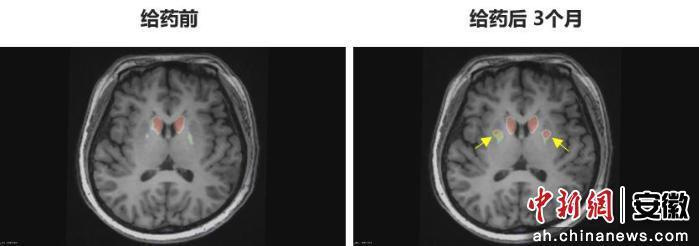

今年6月,李女士在中国科学技术大学附属第一医院接受了NCR201干细胞移植治疗,该疗法利用诱导多能干细胞(iPSC)衍生的多巴胺能神经前体细胞。三个月后,她成为全球首例“功能性治愈”的帕金森病患者。

“身体不僵硬了,像正常人一样。”李女士笑着说。多年的抖动与“关期”彻底消失,她重新感受到身体的轻盈和心灵的自由。术后影像显示,移植细胞已在脑内成功定植并发挥功能,医生称这些“亮点”是新生多巴胺能神经元的直接证据。